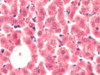

Bile canaliculi - hepatocyte cell membrane (arrowheads) are clearly evidence in this photomicrograph. Note that in fortuitous sections, bile canaliculi (arrows) are recognizable. These bile canaliculi are small intercellular spaces through which bile flows to the periphery of the lobule. Human Liver.

Bile canaliculi - Bile is secreted into bile canaliculi (BC). These channels are formed by the retraction of

the plasma membranes (arrows) of the hepatocytes to produce an open space between adjacent cells. Thus, bile canaliculi are not channels lined by a cell population distinct

from hypatocytes, but are an anastomosing series of tunnels lined y the hepatocytes themselves. Microvilli from the surface of the hepatocytes that form the bile canaliculus entre the channel. Tight junctions (arrowheads) between the hepatocytes seal off the area and prevent leakage of bile into the intercellular spaces.